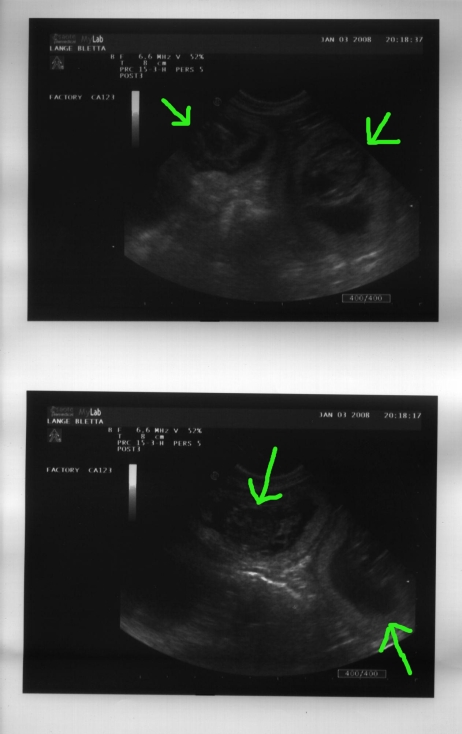

Fast drei Wochen sind seit dem ersten Ultraschall-Termin verstrichen und es läßt mir keine Ruhe - ist noch alles in Ordnung? Zu frisch ist noch meine Erinnerung, als wir die Wurfkiste schon aufgebaut hatten und dann doch keine Welpen kamen. Um meine Nachtruhe (und den Hausfrieden...) zu retten, waren wir heute erneut zum Ultraschall. Ich mochte ja kaum dran glauben - soll dieses Mal wirklich alles gut gehen? Bletta wird immer dicker, obwohl ihre Futterration sich nicht verändert hat, sie hat auch schon zugenommen. Der Ultraschall zeigt deutlich den Grund: Vier Welpen sind sofort zu erkennen, und es sieht aus, als winkten sie uns zu, so sehr zappeln sie herum. Der Berger ist halt keine ruhige Rasse, offensichtlich von Anfang an...

Die ersten beiden Drittel sind schon fast vorbei, jetzt geht's für die Zwerge ans Wachsen.

Ultraschall vom 03.01.2008